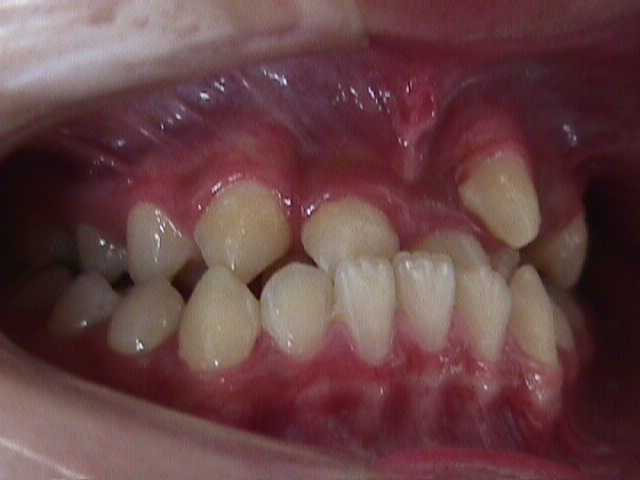

【矯正症例】左上2番3番逆転症例2

Before

左上2番3番逆転症例

随分、前の症例で現在、写真しか残っておりません。

治療費や、治療期間を掲載できないことをご了承ください。

私の矯正歯科医の人生の中でも、特に思い出深い症例です。